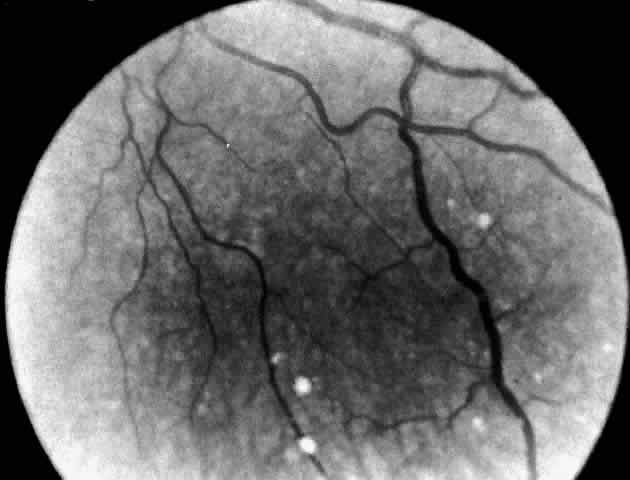

Niemann-Pick disease type A was described by Niemann in 191441 in an 18-month-old Jewish child with hepatosplenomegaly and mental retardation. In 1927, Pick42 described the histopathology characterized by large numbers of vacuolated or “foam” cells in many organs and tissues in the body. Subsequently, Klenk, in 1934,43,44 identified the lipid stored as sphingomyelin. CLINICAL MANIFESTATIONS. Infantile Niemann-Pick disease type A has its onset in early infancy at 6 months of age. The disease is characterized by failure to thrive, a protuberant abdomen due to an enlarging spleen, and severe involvement of the CNS with progressive loss of motor function. Death occurs by the third year of life. Approximately half of these patients are the offspring of Ashkenazi Jews. In Niemann-Pick disease type B, only visceral involvement is noted. Onset is in late childhood between 3 and 11 years of age or in adult life with splenomegaly and pulmonary infiltrates. Intellect is normal. Infants affected with type B are of mixed ethnic background. Niemann-Pick disease type C, the subacute form, presents in infancy with neonatal hepatitis or later in childhood with moderate splenomegaly and gradual neurologic deterioration. Many patients have seizures and limitation of vertical gaze. The presence of down-gaze paresis is the most typical defect. Sea-blue histiocytes in the bone marrow are common. These patients usually die before the end of their second decade. Niemann-Pick disease type D is clinically similar to type C. This designation is limited to an inbred group of cases traced to a couple who lived in Yarmouth County in Nova Scotia in the late 1600s.45 These patients store sphingomyelin in the tissues in variable amounts. They present with hepatosplenomegaly at 4 to 6 years of age and follow a protracted course. Involvement of the CNS occurs late. Many patients become ataxic and develop seizures. The type E phenotype is characterized by adult onset, mild splenomegaly, foam cells in the bone marrow, and the absence of neurologic signs. OCULAR MANIFESTATIONS. Niemann-Pick Disease Type A. A cherry-red spot of the macula is present in 50% of cases.46 Cogan47 noted no distinction between the appearance of the cherry-red spot in infantile Niemann-Pick disease and that seen in Tay-Sachs disease. Others have reported subtle differences in the color of the fovea and/or the halo and in the degree of opacification of the peripheral retina.48–51 All infants with Niemann-Pick type A disease become blind late in the course of the illness, and optic atrophy develops. Walton and associates51 also noted subtle lens opacities and peculiar corneal clouding, suggesting widespread ocular involvement in this disorder of sphingolipid metabolism. Niemann-Pick Disease Type B. A unique retinal abnormality, the macular halo syndrome has been reported in seven cases of Niemann-Pick disease type B, three enzymatically proven52–54 and four prior to enzyme verification described between 1950 and 1970.55–58 Symmetrical punctate crystalloid ring-form opacities about the foveas were observed in each case with no visual impairment. Cogan and Federman56 in one of the early cases were the first to publish a fundus photograph of the macular halo (Fig. 6). The patient was a 24-year-old woman with hepatomegaly, no neurologic signs, and a reticuloendotheliosis of unclassified type. Both fundi showed doughnut-shaped opacities about the foveas. The opacities were described as yellowish white scintillating granules forming a relatively sharp border on the inner edge of the ring and a ragged border on the outer edge of the ring. Despite this condition the patient had normal visual acuity (20/15 [6/5]) and no scotoma. The first case verified enzymatically was reported by Harzer and associates in 1973.52 The assay showed a sphingomyelinase level in leukocytes that was less than 10% of normal. Although these scattered reports were in the literature, it was Cogan who clearly identified the lesion and made the association with Niemann-Pick disease type B. Cogan and co-workers53 reexamined their initial patient and added a 21-year-old man with a history of splenomegaly and hyperlipidemia. The diagnosis of Niemann-Pick type B disease in each of these patients was confirmed by finding significantly lower sphingomyelinase levels in cultured skin fibroblasts. They named the condition macular halo syndrome. In these cases, the opacities in the retina formed a halo approximately one-half disc diameter at their outer edge. The halo had a crystalloid appearance. By stereo-ophthalmoscopy, slit lamp biomicroscopy, and fluoroangiography the opacities appeared to occupy various depths of the retina but were most numerous in Henle's fiber layer, causing only minor obscuration of the overlying vessels. The foveal lesion in Matthews and associates' patient54 is similar in size and appearance to the fundus photograph published by Cogan and coworkers. On the basis of stereo biomicroscopy and contact lens examination, Matthews and associates located the lesion in the ganglion cell layer of the retina. The masking effect that the ring lesion had on the perifoveal vasculature in the early fluorescence angiogram was taken as confirmation that the accumulated material is in this superficial layer of the retina. As a result, Matthews and associates proposed that the macular halo represents the smallest or mildest form of a cherry-red spot—findings in conflict with those of Cogan. The precise location of the opacities in the retina remains uncertain, however, because of the lack of histopathology. The available clinical data suggest that such opacities are permanent. For example, the appearance of the macular halo remained unchanged for 15 months in one case,57 4 years in another,52 and more than 20 years in one of Cogan's cases.53 Cogan concluded that the remarkable preservation of normal visual function in all of the cases either was due to hiatuses in the opacities or, less likely, to a localization of the opacities behind the photoreceptors. Niemann-Pick Disease Type C, In Niemann-Pick disease type C neither the macular cherry-red spot nor the macular halo syndrome has been observed. However, differentiating Neimann-Pick disease type C from the other types of Niemann-Pick disease is a clinical syndrome that has been referred to in the literature as ophthalmologic neurovisceral lipidosis,59 vertical supranuclear ophthalmoplegia lipidosis,60–63 and Neville's disease.64 Cogan and co-workers65 have added nine cases to the 30 patients already reported Under these various headings and have recommended an acronym, the DAF syndrome, to denote the three essential features: downgaze paralysis, ataxia/ athetosis, and foam cells in the spleen, liver, and bone marrow. Characteristic of the Niemann-Pick disease type C DAF syndrome is an onset in the first 2 decades of life. There is a characteristic progression of the down gaze paralysis to involve upgaze and eventually horizontal gaze and a total supranuclear ophthalmoplegia. Athetosis and spasticity develop in addition to ataxia. There is extensive infiltration of bone marrow, spleen, liver, and other tissues with foam cells and a variable degree of intellectual impairment. Sphingomyelinase activity in leukocytes and cultured fibroblasts is decreased or normal. The underlying metabolic block is reported to be in the esterification of cholesterol within the cells. Niemann-Pick Disease Types D and E. Niemann-Pick type D disease has no ocular manifestations. Patients with the type E variant may have macular cherry-red spots. NEUROPATHOLOGY. In Niemann-Pick disease sphingomyelin accumulates in excess in the brain and autonomic ganglia. The neurons appear swollen with pale cytoplasm. Ultrastructurally the cells contain concentric lamellated bodies representing storage cytosomes. Inclusion profiles in the viscera, lymph nodes, and foam cells also correlate with an increase in sphingomyelin content. In the eye in Niemann-Pick disease type A with macular cherry-red spots, stored lipid is localized to the ganglion and amacrine cells of the retina most obviously in the parafoveal region. The ganglion cells of the other nuclear layers are unaffected.66 Larsen and Ehlers67 report, however, that the affected ganglion cells are not ballooned, degenerated, or reduced in number. This may account for the retention of vision in their patient and in similar nonblind infants despite the presence of a cherry-red spot at the macula. Degenerated, necrotic engorged ganglion cells, interspersed with structurally intact lipid-laden ganglion cells, have been described by others.66 It appears that the retinal ganglion cells in Niemann-Pick disease are conspicuously unlike those in Tay-Sachs disease in their ability to tolerate the presence of excess intracellular lipid so well. In frozen sections of formalin-fixed retina, both ganglion cells and amacrine cells show marked granular cytoplasmic birefringence. In the study by Robb and Kuwabara68 frozen sections of other portions of the eye revealed a remarkably wide distribution of storage material giving the granular birefringence. Corneal stromal cells were markedly positive, as were corneal endothelium and lens epithelium. The vascular endothelium, the nonpigmented epithelium of the ciliary body, and the retinal pigment epithelium were uniformly birefringent. Electron microscopic examination of the cornea and retina showed the lipid stored was in the form of membranous cytoplasmic bodies (Fig. 7).68 The distribution of these inclusion bodies is similar to that of the birefringent material seen on light microscopy. The bodies are most abundant in retinal ganglion cells and retinal pigment epithelium. They are present in moderate numbers in corneal stromal cells, lens epithelium, corneal endothelium, vascular endothelium, and the sphincter muscle of the iris. They are infrequent in Müller cells, glial cells, and rod and cone inner segments. The morphology of the membranous cytoplasmic bodies found in the eye in Niemann-Pick disease type A corresponds closely to the previously reported ultrastructure of lipid inclusions in the brain and viscera in other patients with Niemann-Pick disease type A. An ocular ultrastructural study of a 23-week-old fetus with Niemann-Pick disease type A also demonstrated rather extensive ocular involvement.69 In the eye in Niemann-Pick disease type C, Palmer and colleagues70 observed extensive lipid storage in ocular tissues. Intracellular pleomorphic cytoplasmic bodies were visualized in the conjunctiva, cornea, lens, retinal ganglion cells, and retinal pigment epithelium and in optic nerve astrocytes. Only the pathology of the optic nerve and retinal ganglion cells correlated with the clinical findings of optic atrophy and a perimacular gray discoloration. DIAGNOSTIC TESTS. The diagnostic test in Niemann-Pick disease type A and type B is measurement of sphingomyelin activity in leukocytes or cultured skin fibroblasts. The enzyme is deficient in both types. Prenatal diagnosis has been accomplished by assaying cultured amniotic fluid cells in type A and type B.71 In Niemann-Pick disease type C the metabolic block is in intracellular cholesterol esterification. Cultured fibroblasts from affected persons store high levels of unesterified cholesterol. This is the basis for the laboratory diagnosis of Niemann-Pick type C. Carriers are also identified by this test. The underlying metabolic defect in Niemann-Pick type D and type E disease is still not understood, but these two variants are not diagnosable by a single laboratory test. Increase in organ sphingomyelin content and/or presence of foam cells in the bone marrow help to corroborate clinical suspicions. |